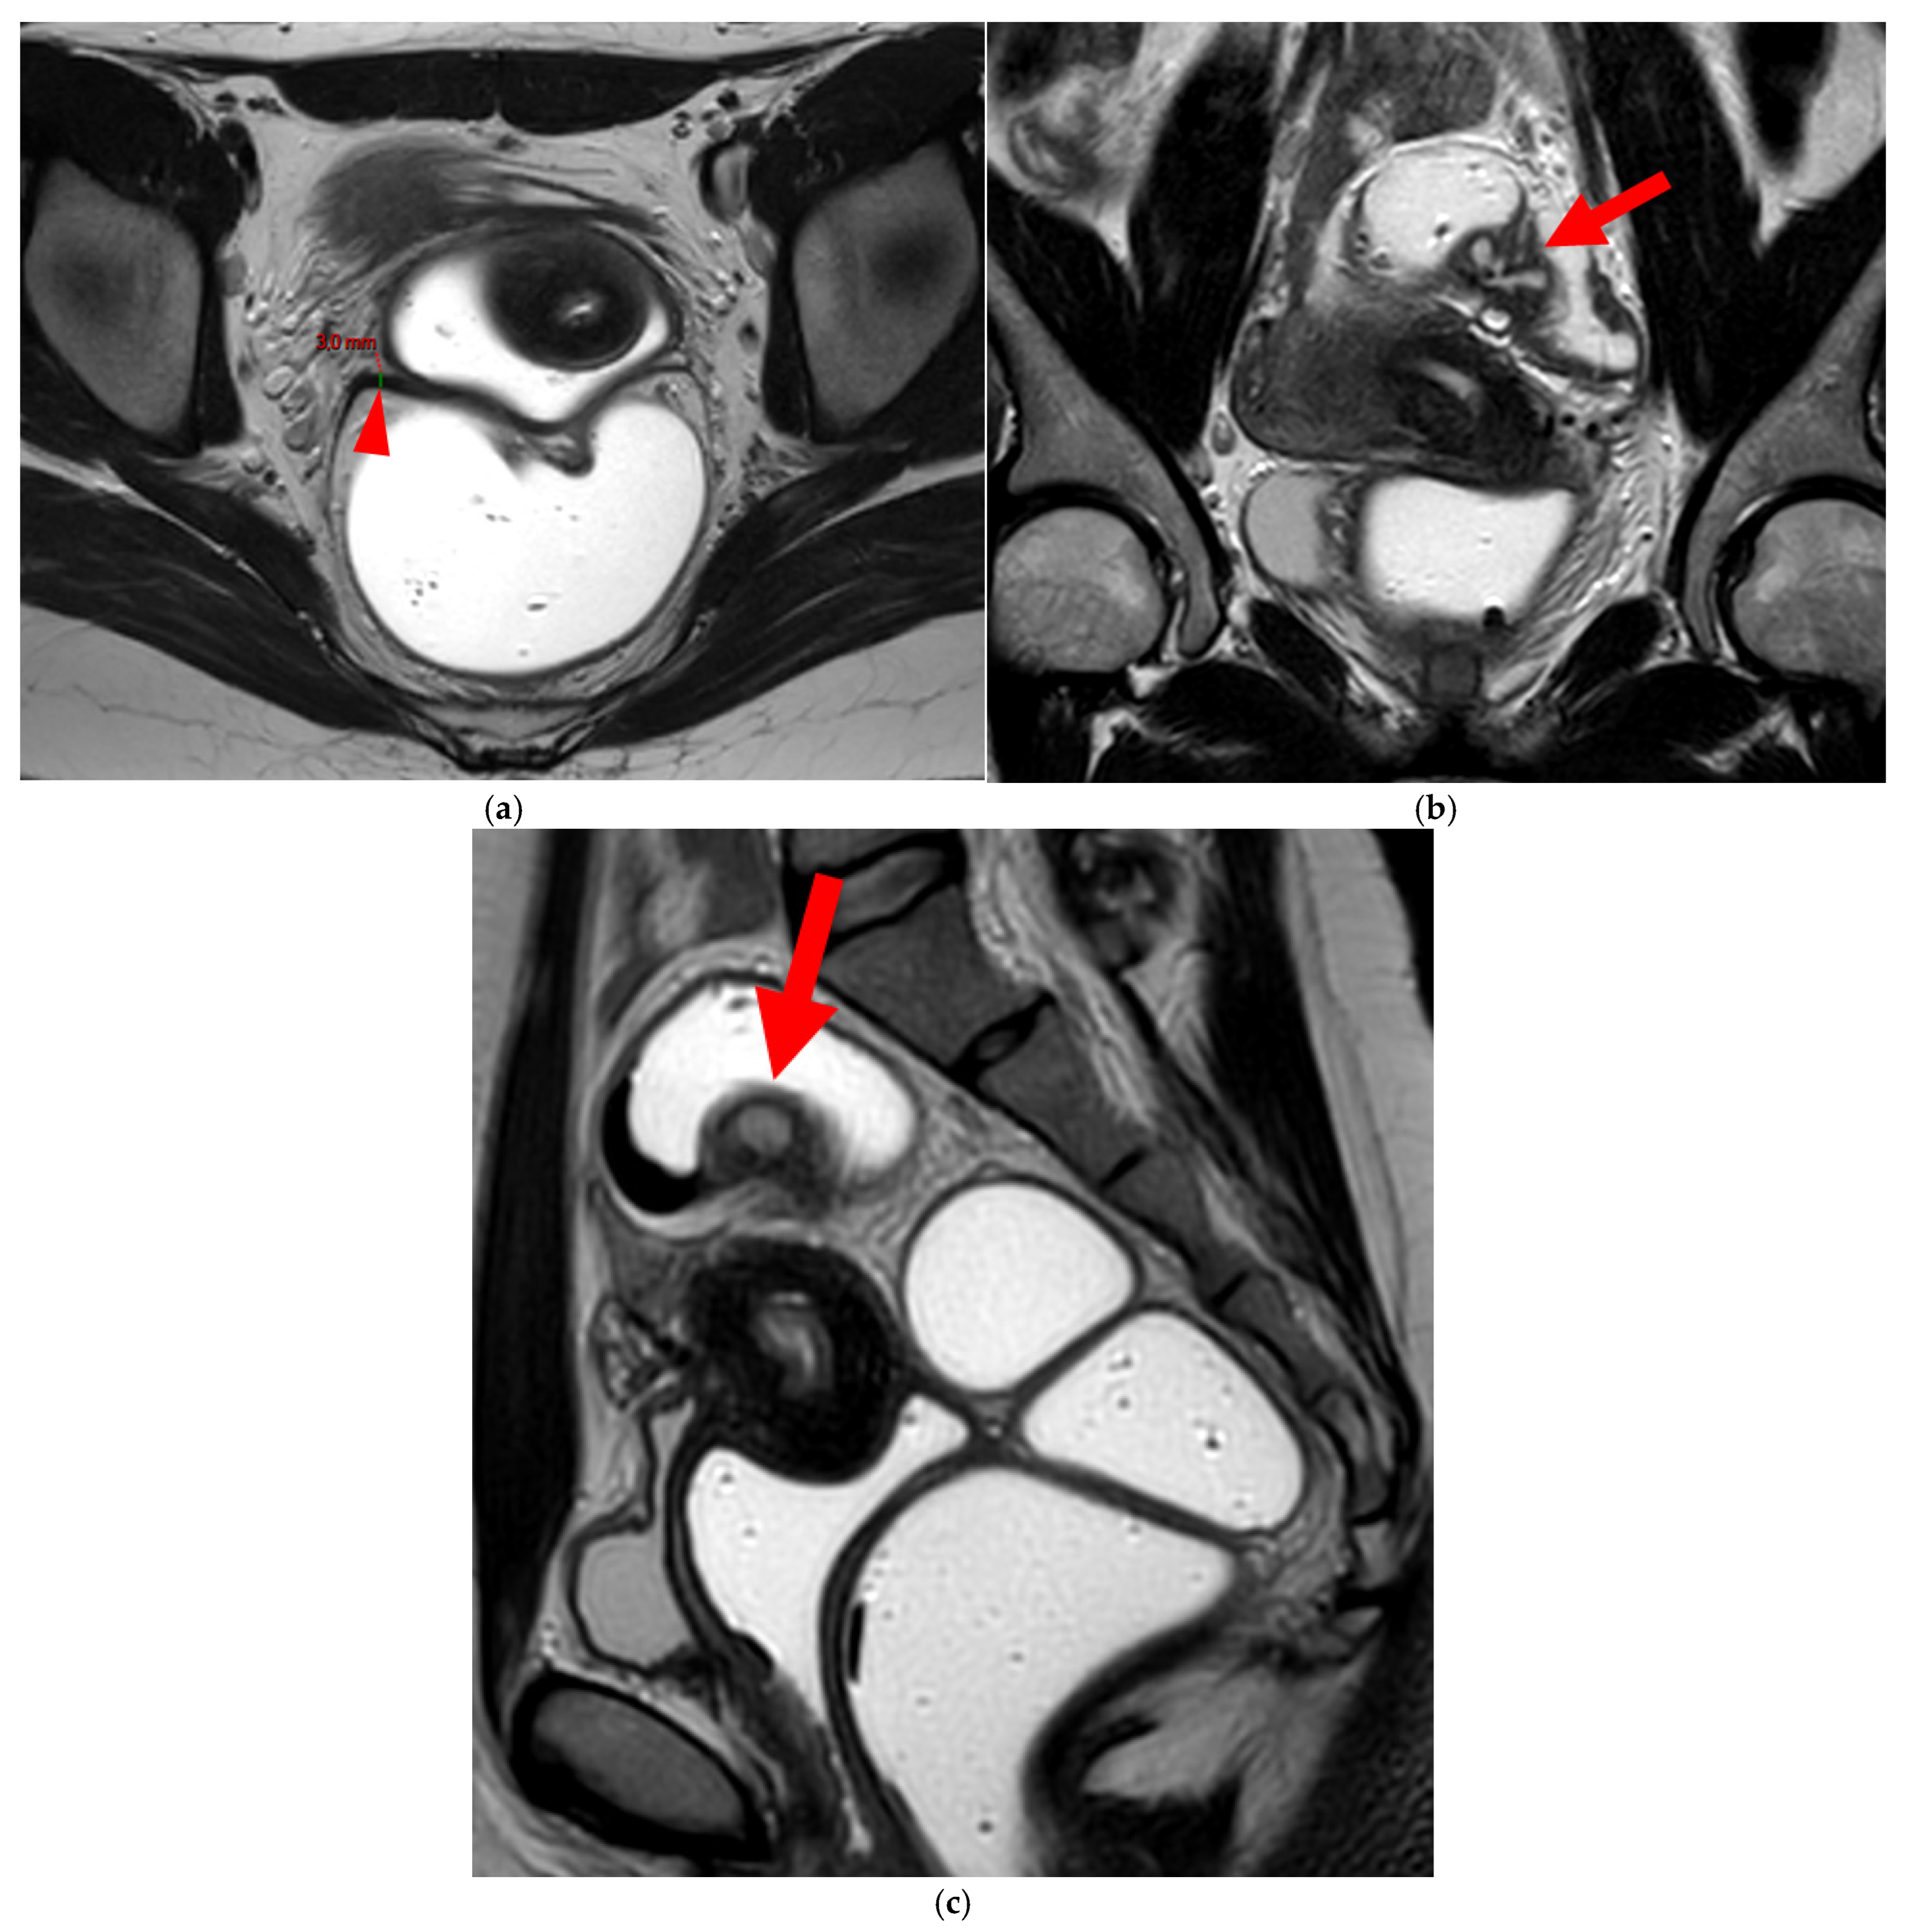

A type 5B USL (Figure 7) is nodular with spiculated margins. A type 5B USL may also display an isolated nodule with microcystic content.

Figure 7. Pelvic MRI scans of two patients with HTD type 5B USLs. (a) Patient 1: sagittal T2WI shows a microcystic nodule (arrow) within the origin of the right USL (arrowhead). (b,c) Patient 2: axial (b) and sagittal (c) T2WI show a nodular left USL with spiculated margins (arrow) and a right ovarian endometrioma (arrowhead).